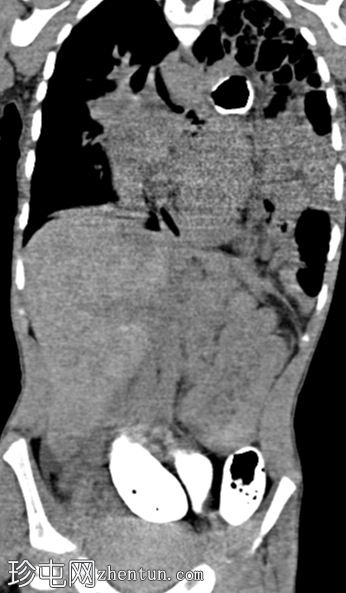

斜位

消化道造影检查显示食管口径正常,胃明显延长,延伸至盆腔区域。

左胸腔可见囊性透亮区,与腹部相连,导致心脏轮廓向右侧移位。